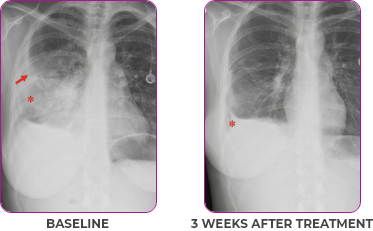

Response in primary and metastatic lesions1

MRIa imagery of the lungs. Arrow indicates large target lesion in left lung.1

SCAN 1: LUNG

MRIa imagery of the brain. Arrow indicates large target lesion in left lung.1

aMRI, magnetic resonance imaging.

Images courtesy of Dr Fabian Pitoia.

- Partial response and symptom improvement confirmed by chest X-rays after <1 month of treatment

- Imaging performed 6 weeks into treatment revealed considerable decrease in the size of both target lesions

Lung imaging of primary tumors.

SCAN 2: LUNG AND BONE

Images courtesy of Dr Maximilian Hochmair.